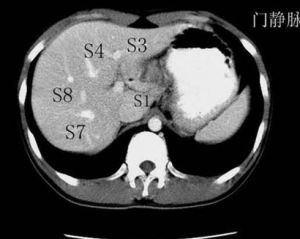

Couinaud根据门脉系统肝段按顺时针方向标以罗马数字从ⅠⅡⅢⅣⅤⅥⅧ,其中左内叶及尾状叶不再分段。 肝脏分8个段,主要被肝静脉系统和门静脉系统分割。肝中静脉将肝分成左右两叶。肝右静脉分肝右叶为右前、右后两部分。肝左静脉分肝左叶为左内叶、左外叶。门静脉系统走行于肝段内。Ⅰ段为尾状叶,CT示在门、腔静脉之间,Ⅱ段(靠上)与Ⅲ段(靠下)构成左外叶,Ⅳ段为方叶,也是左内叶,Ⅴ段(靠下)与Ⅷ(靠上)段构成肝右前叶,Ⅵ段(靠下)与Ⅶ段(靠上)构成肝右后叶。至于Ⅱ段与Ⅲ段、Ⅴ段与Ⅷ段、Ⅵ段与Ⅶ段分界,粗略方法以肝内门静脉分支或肝门平面为分界标志,出现以上平面所显示的是靠上方的,Ⅱ段、Ⅶ段、Ⅷ段,以下层面就是Ⅲ段、Ⅴ段、Ⅵ段。Ⅴ段与Ⅵ段、Ⅶ段与Ⅷ段之间以肝右静脉分界。影像学上横断面上以肝静脉为界,2,3;5,8;6,7 的分界大约门静脉左右分支平面。 医学百科网 | YxBaike.Com

1、肝脏分段的意义:可以了解病灶所处位置,尤其对于肝脏恶性肿瘤患者,从而指导治疗。肝脏的分段和肝脏的解剖密切相关,了解了肝脏的解剖并且应用到影像学的分析中去,也就可以熟练的了解肝脏的分段了。 2、分段主要依靠CT。 CT:首先找出肝脏的三大静脉:肝中静脉,肝左静脉,肝右静脉;找出门静脉及其分叉部位。门静脉分叉可以区分上段和下段,即肝S5/S8,S6/S7,门静脉分叉以上为S8,S7;肝右静脉和肝中静脉之间是右前叶,肝右静脉以后是右后叶;一般规律,从CT上看,最先看到的是S8,然后是S2、3,肝左外叶以肝裂为界,比较容易辨认,左内叶为肝裂和肝中静脉之间区域,胆囊往下的层次是S5,最后的层面一般是肝S6,下腔静脉和门静脉夹着的是尾状叶,即S1。